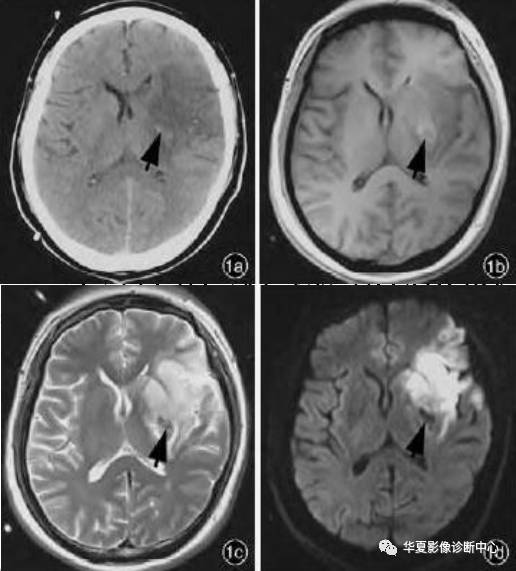

细胞毒性脑水肿

好发于急性期缺血性脑血管病,多累及灰白质。

主要机制是:不同的致病因素,使细胞内外环境改变,脑组织缺氧,细胞代谢障碍,ATP生成减少,钠-钾泵异常,钠在细胞内潴留,细胞内渗透压升高,细胞外间隙的水分子进入细胞内,造成细胞肿胀,细胞外间隙狭窄。

MR表现:脑沟变窄,脑回肿胀,模糊,FLAIR序列皮质高信号。DWI高信号,ADC明显降低。